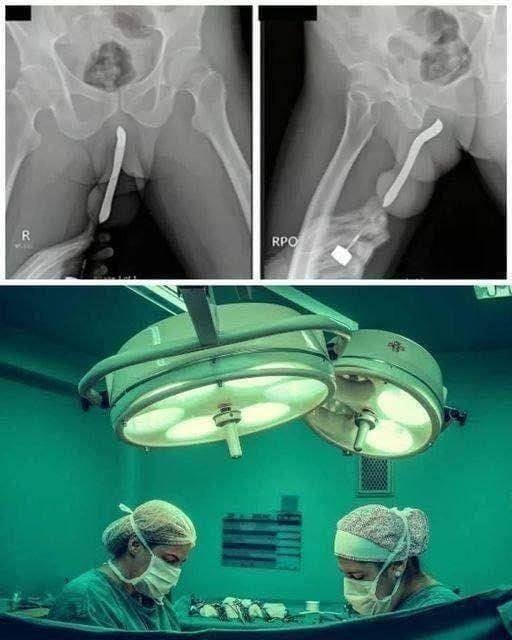

pen caused internal lacerations and significant tissue damage, which led to bleeding, pain, and the risk of infection. She was quickly taken to the hospital, where doctors performed an emergency surgery to remove the foreign object and prevent further complications.

Medical staff were able to stabilize her condition, but experts warn that the situation could have easily resulted in permanent damage to reproductive organs, life-threatening infections like sepsis, or even death had she not received urgent care.